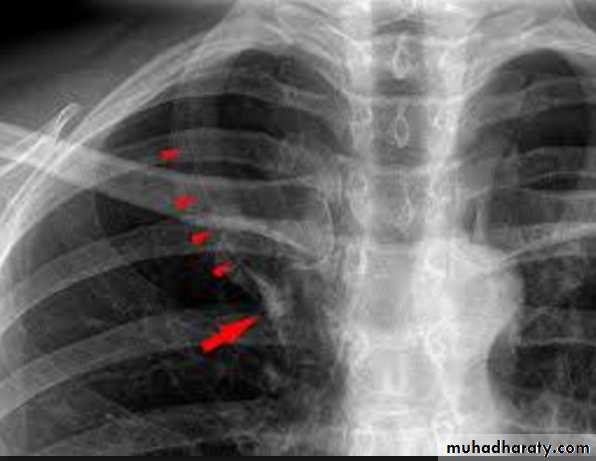

Rib notching should be noted as it may indicate coarctation of aorta.

Rib notching coarctation of aorta